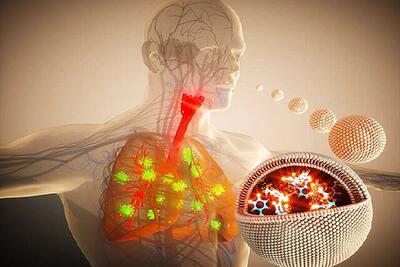

چراغ سبز FDA به یک داروی استنشاقی نانویی برای عفونتهای باکتریایی ریه

به گفته این شرکت، شرکت تابعه آنها به نام EVOQ NANO ، موفق به پاسخگویی به موارد مطرح شده توسط سازمان غذا و دارو شده است.